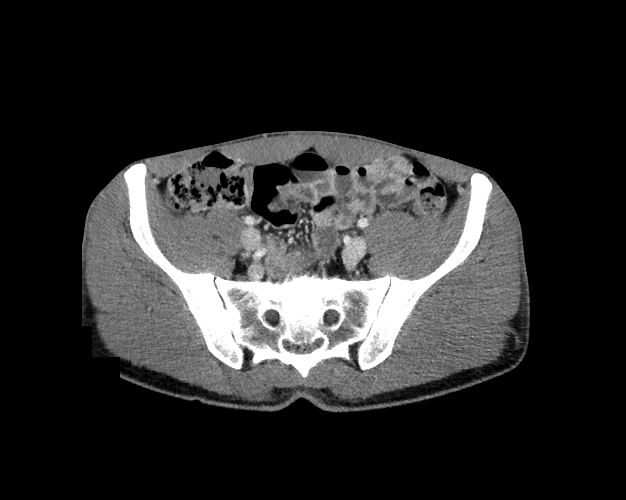

Body

Covers abdominal CT anatomy.